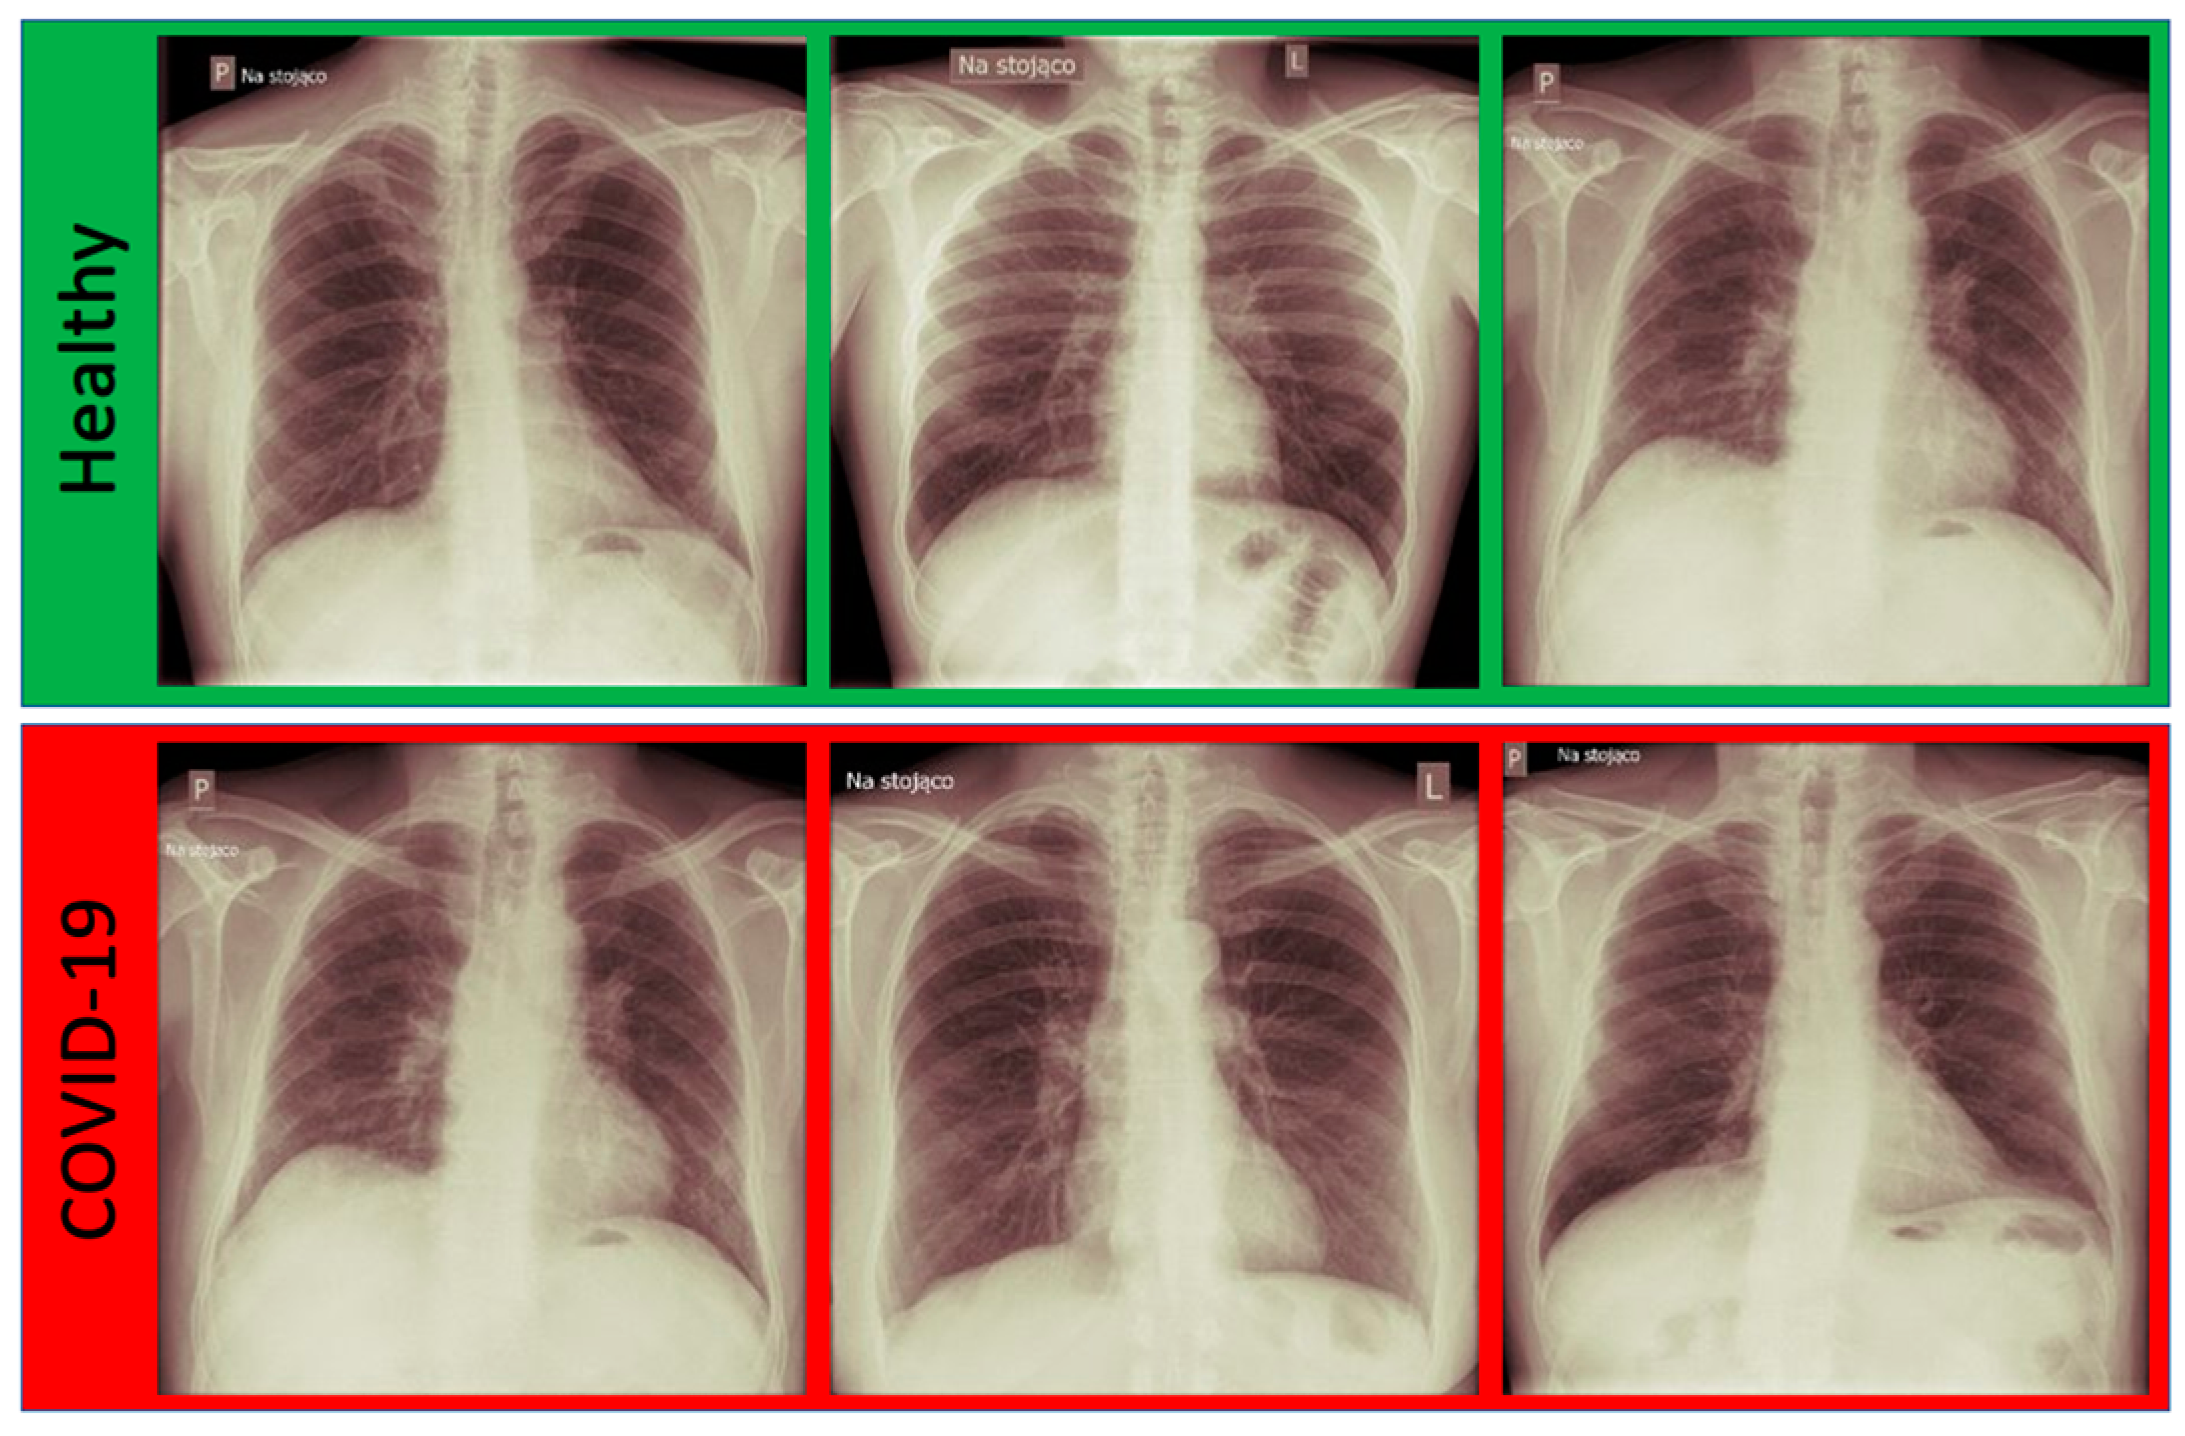

3.1. Dataset